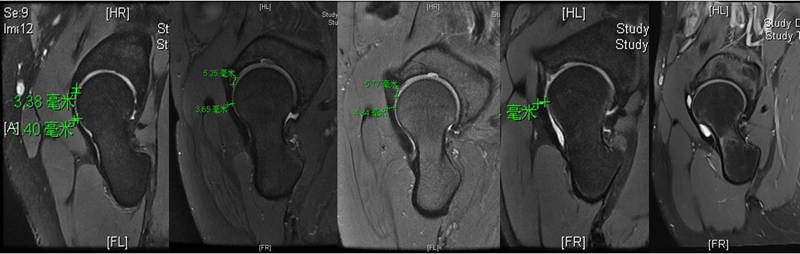

对这些测量数据进行统计学分析后发现DDH组的厚度均值是3.2,BDDH组是4.5,FAI组是4.7。统计学意义上来讲DDH组和BDDH组是有差异的,但是BDDH组和FAI组两者是没有差异的。但是在关节囊内信号分级上,这每两组之间都是有差异的。这也说明从厚度上来讲,DDH病人会导致前关节囊变薄,但是BDDH病人虽然没有观察到厚度的变化,但是也已经出现了囊内信号退变性的表现,我们称之为关节囊内部的水肿或者是分层表现。

同时,也通过关节镜下进行了评估和测量。采用关节囊纵切的方式,就有机会测量到关节囊中段的厚度。通过镜下测量发现,BDDH组和FAI组的中位值分别是6mm和7mm。

通过对于关节囊厚度和关节囊信号的测量,是否存在一个能够帮我们区分哪些患者倾向于稳定,哪些患者倾向于不稳定这样的一个截断值?我们通过一个病例设定截断值大概在4mm,通过观察发现,在<4mm的病例主要集中在DDH,而基本上所有BDDH和FAI病人的关节囊厚度都是>4mm的。所以我们提出一个预先的、简洁的记忆标准,即4mm可能作为判断关节囊是否比较薄,启示关节囊不稳定的一个数值。